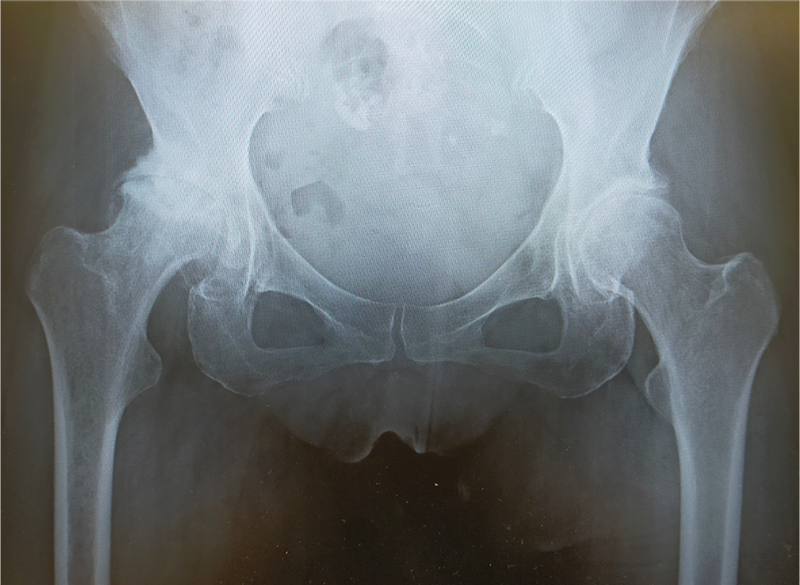

〈手術前のレントゲン〉

〈手術後のレントゲン〉(正面)

当院にて両側の人工股関節全置換術(THA)を施行。アプローチはAMIS(前方最小侵襲手術)で行い、術中に神経ブロックを併用することで、術後の疼痛コントロールを行い、術翌日から離床、リハビリを進めることができました。術後すぐに歩けることに本人も驚いていました。また、術後は一切の肢位の制限も行っていません。